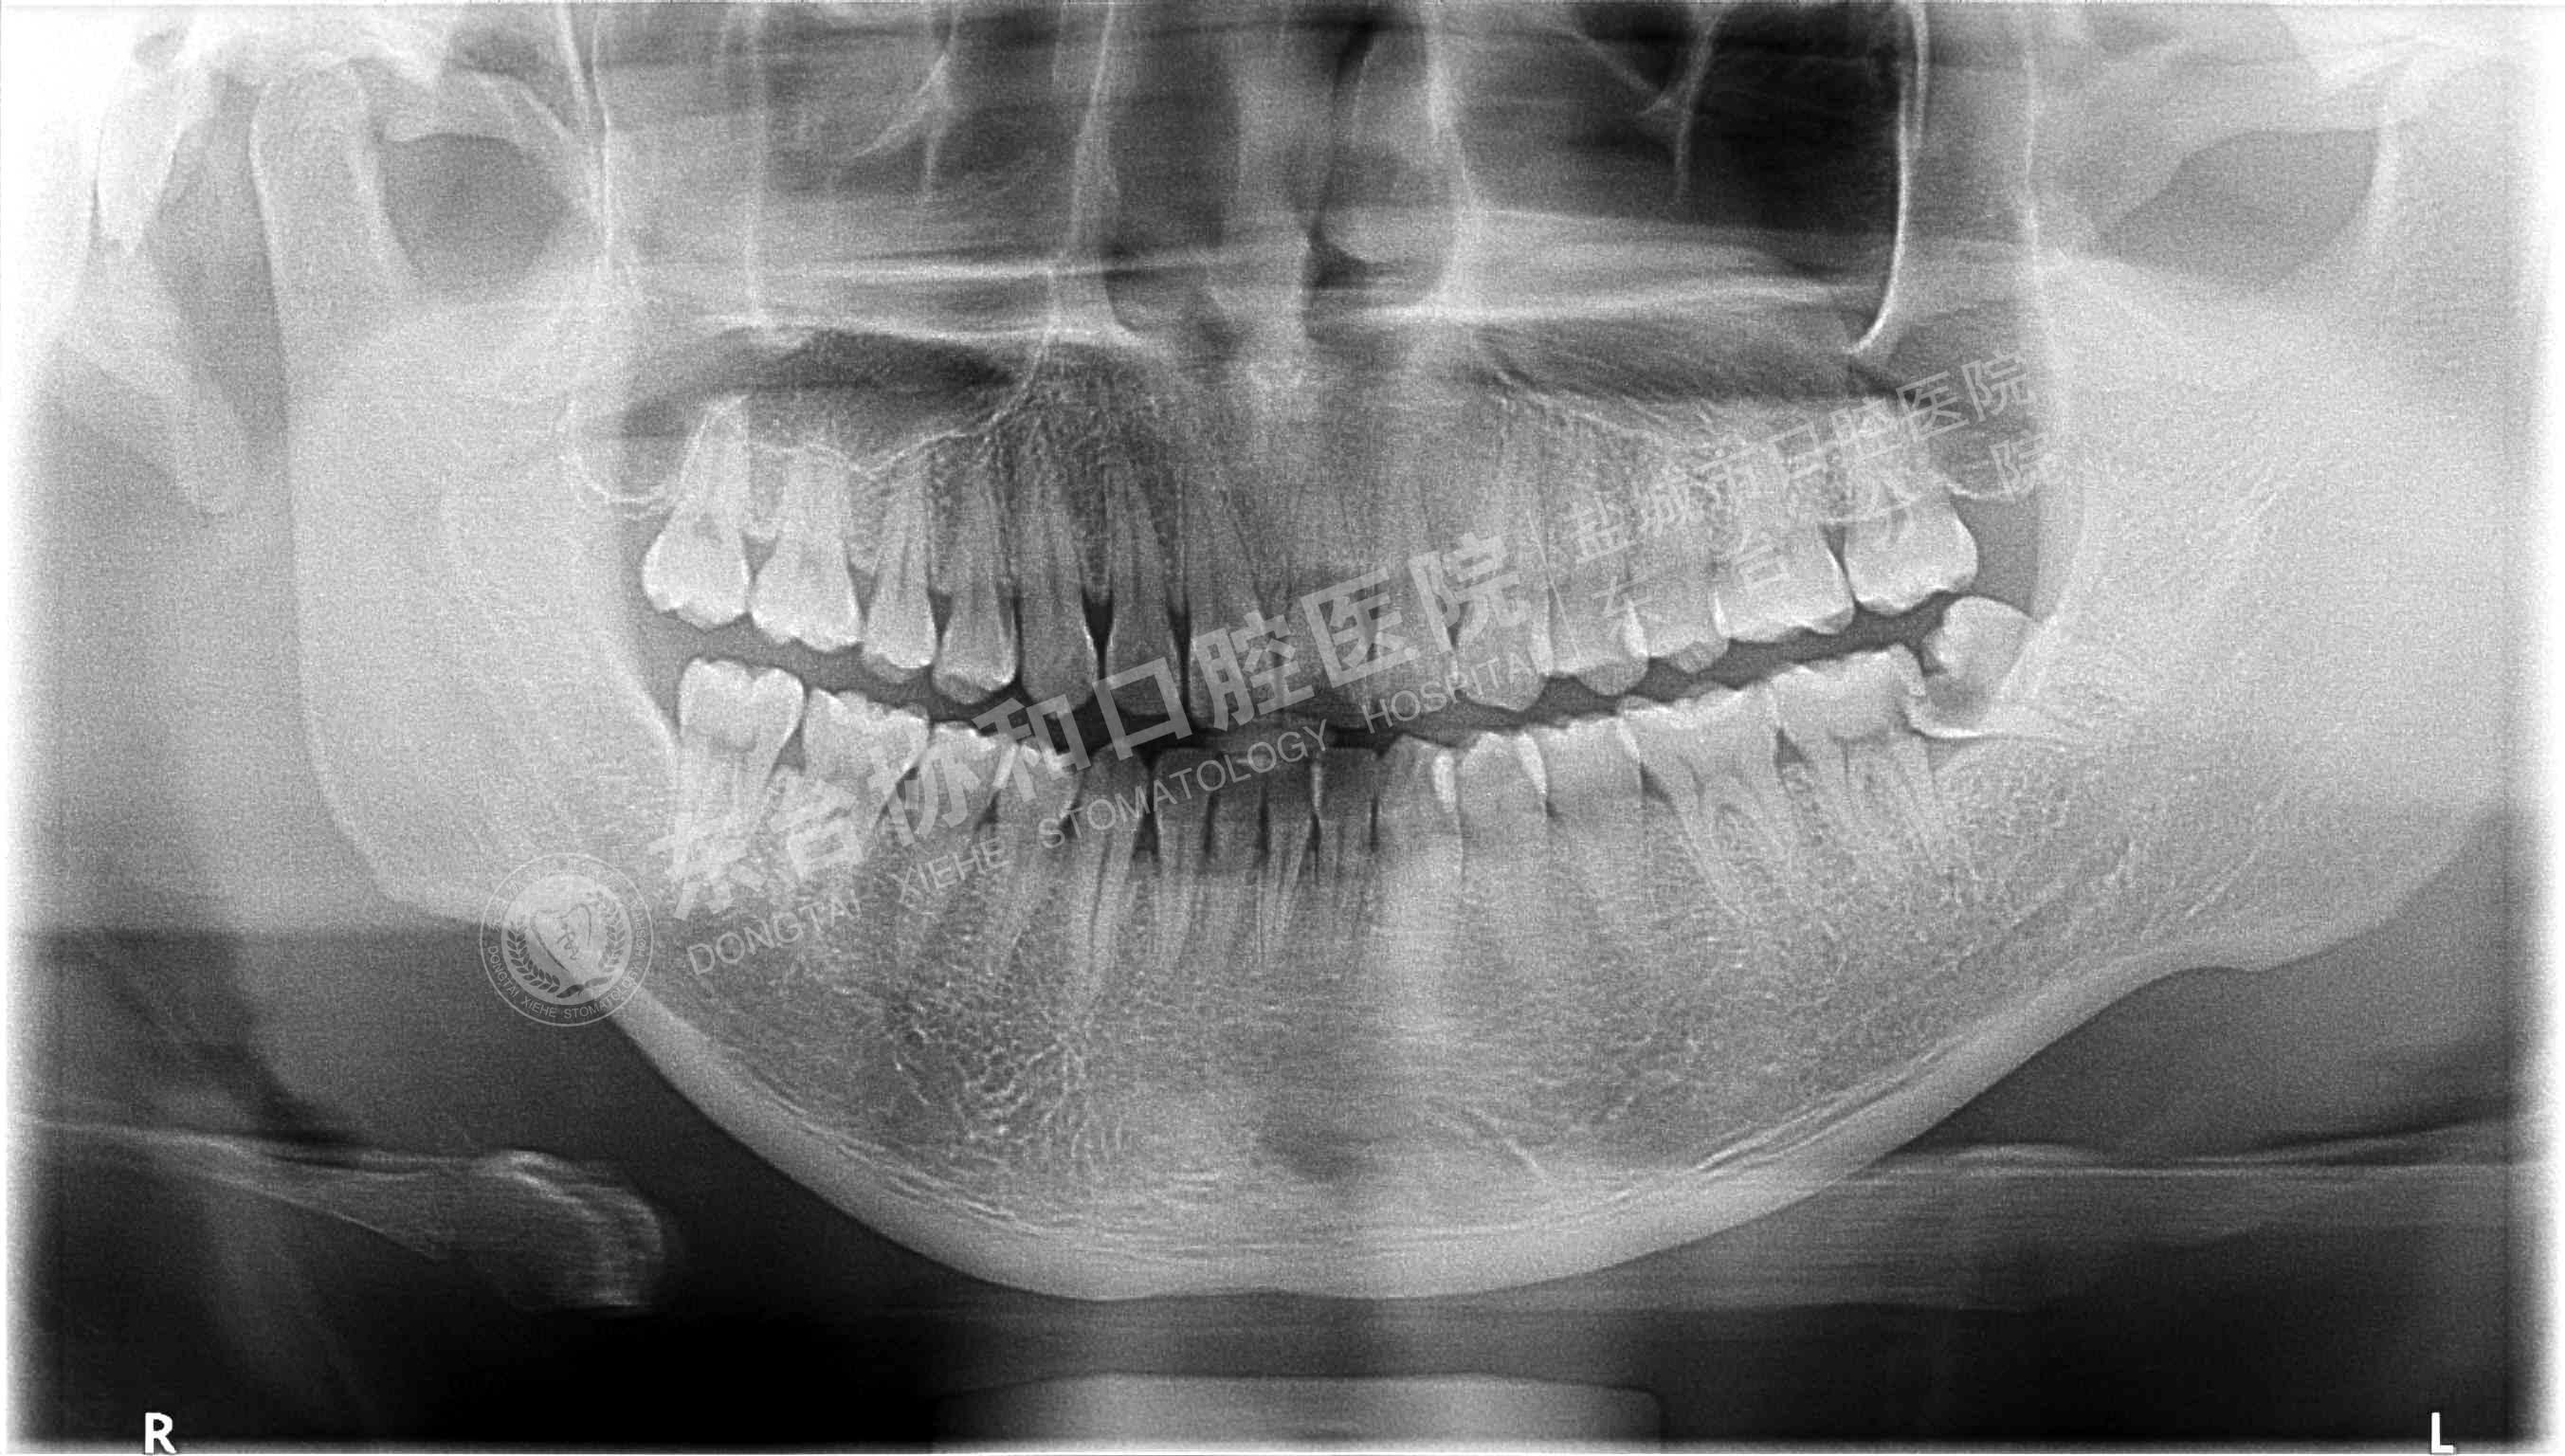

很多患者都很排斥拍牙片,認(rèn)為醫(yī)院是為了多收錢才讓他們拍的,其實(shí)這是一個(gè)錯(cuò)誤的想法,拍牙片是口腔科常用重要的檢查手段,臨床檢查只能直觀判斷牙冠和牙齦部分的情況,而對(duì)于牙根,牙槽骨、牙周膜等情況則必須通過牙片檢查。牙齒在牙片上顯示出白色阻射影像,其中牙釉質(zhì)阻射強(qiáng),牙本質(zhì)和牙骨質(zhì)阻射低于牙釉質(zhì),牙髓腔呈灰黑色影像,根管口至根尖孔呈逐漸變細(xì)的影像。

通過牙片除了了解牙齒的病變情況,還可以了解牙槽骨內(nèi)是否有埋伏牙、多生牙、牙源性腫瘤和囊腫等,依據(jù)牙片綜合分析可以提高牙齒診斷調(diào)節(jié)的準(zhǔn)確性和。

6、用于阻生牙、埋伏牙及替換牙的檢查和調(diào)節(jié)。

7、牙片來確定乳牙和恒牙的相對(duì)位置,用來幫助醫(yī)生診斷乳牙是否能自行脫落還是需要拔除。